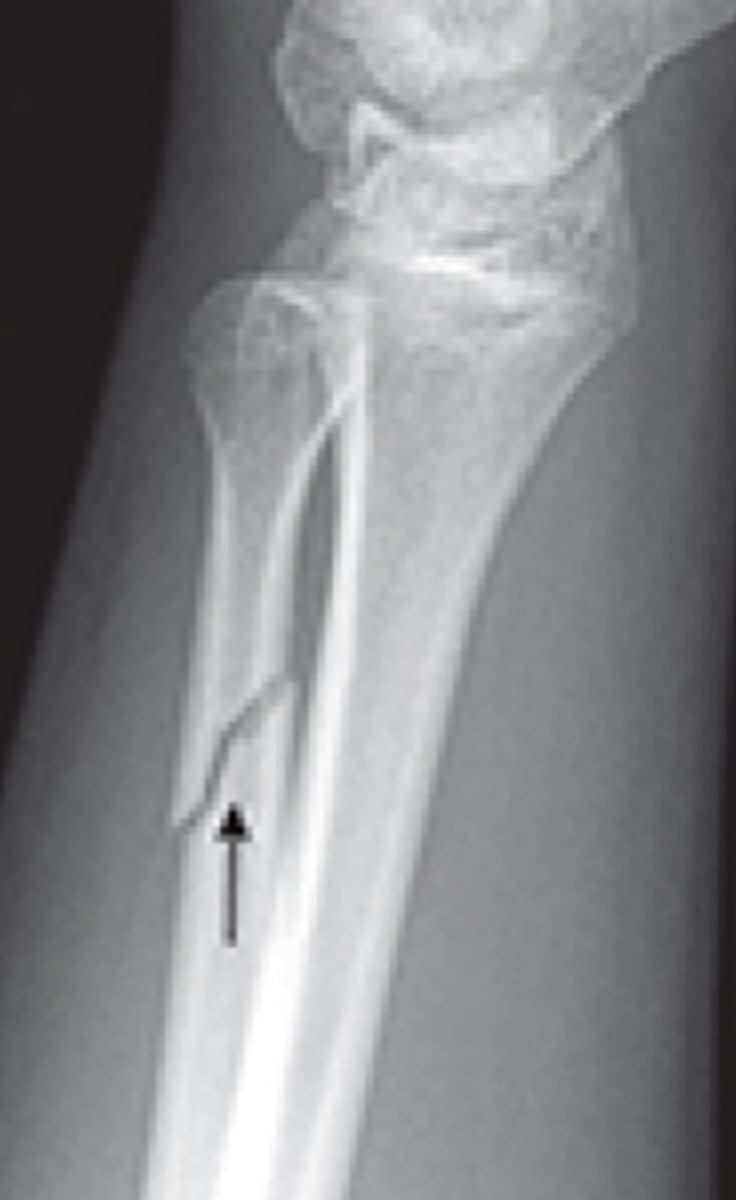

transverse fracture line

fracture is perpendicular to bone axis

oblique fracture line

fracture occurs diagonal across bone axis

spiral fracture line

torsional fracture that spirals around bone, often due to twisting